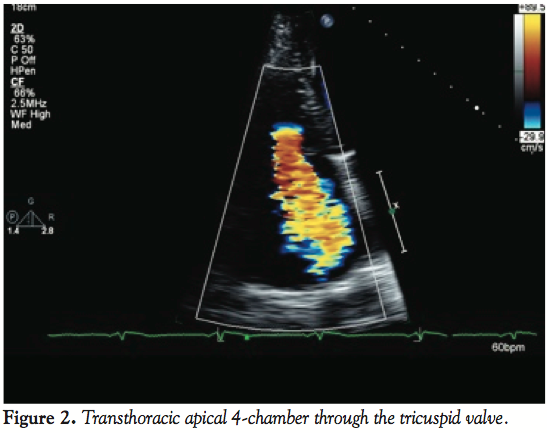

mild shortness of breath. Later that evening, he visited the office of a relative who was a community cardiologist. An EKG demonstrated diminutive R waves in III and aVF, and T-wave inversions in the same leads. There were no ST-T wave segment changes (Figure 1). A transthoracic echocardiogram in the office demonstrated severe tricuspid regurgitation (Figure 2). The patient was directly admitted to the hospital for further cardiac evaluation.

On arrival to the emergency room, vitals were normal; blood pressure was 132/84 and pulse was 63 bpm. A III/VI systolic murmur was noted in the left sternal border. Lungs were clear to auscultation, and the remainder of the exam was normal. The patient underwent a transesophageal echocardiogram (TEE) to evaluate the severity and mechanism of the regurgitant lesion. The TEE revealed moderate right ventricle (RV) dilatation and a distinct akinetic anterior wall of the RV. The severe tricuspid regurgitation was due to tethering of the leaflets, secondary to the underlying wall motion abnormality (Figure 3). The wall motion in other regions was preserved and there were no other accompanying valvular abnormalities.